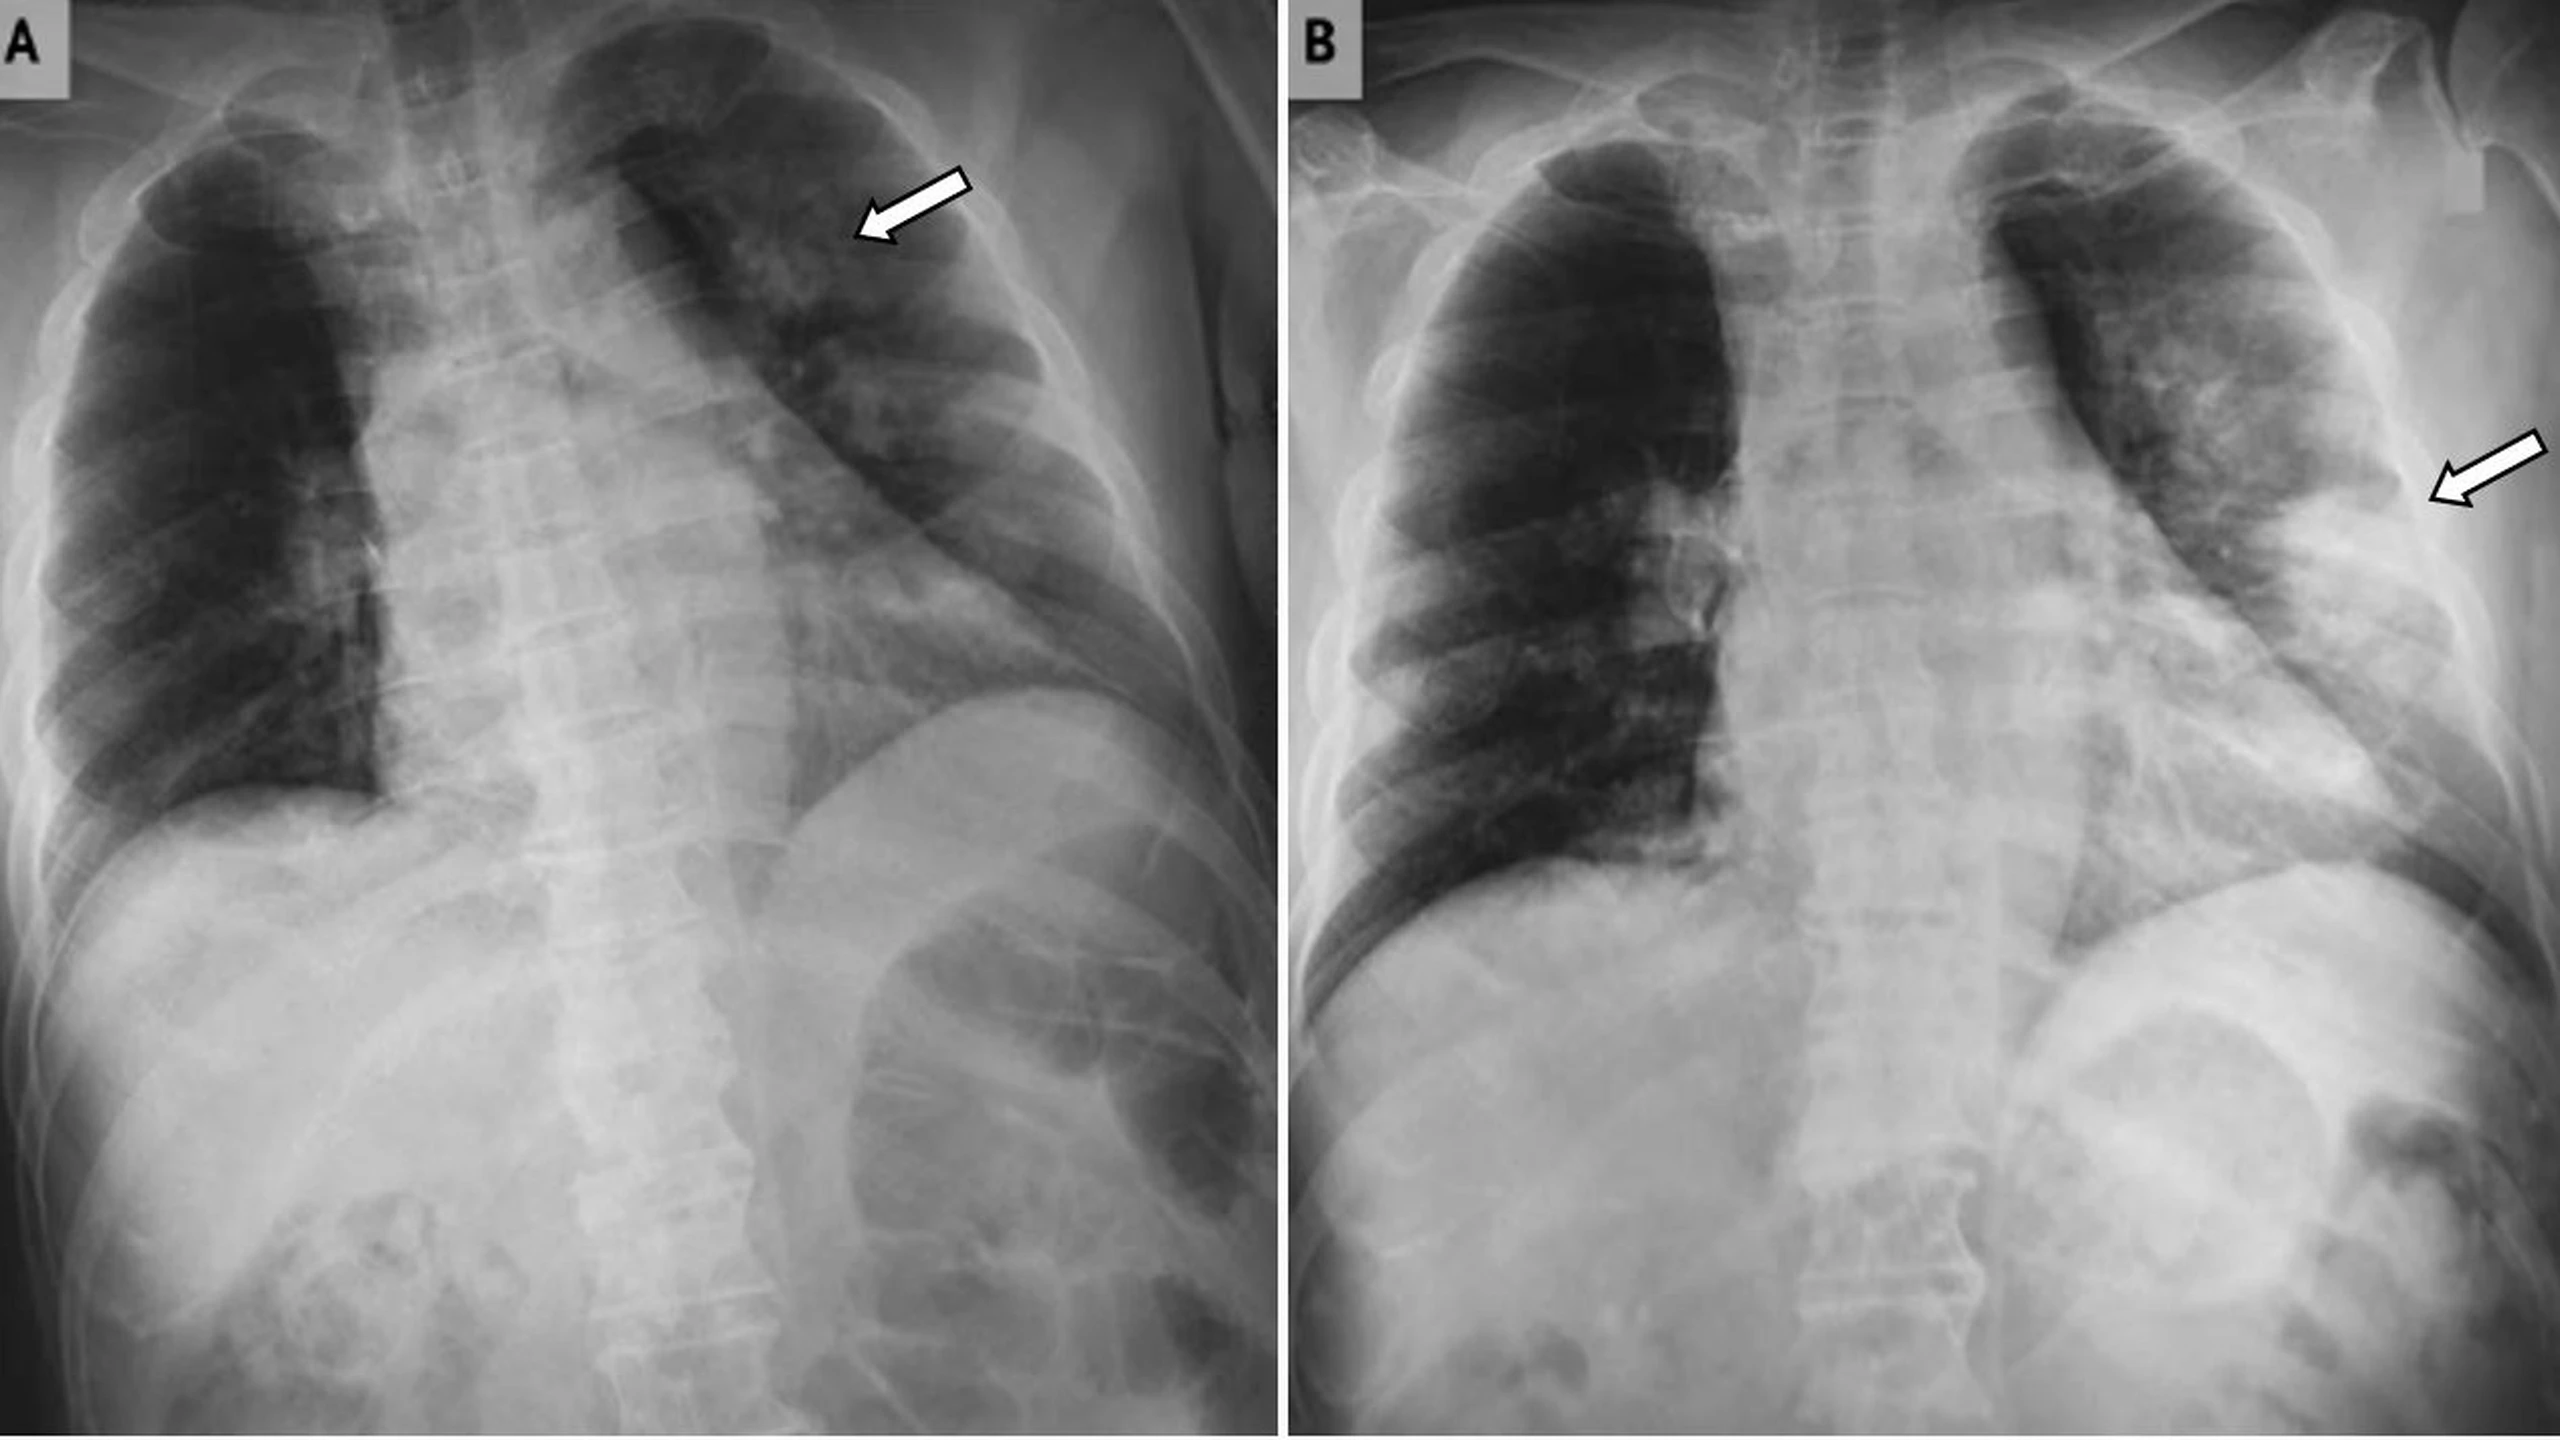

Bệnh tích protein phế nang (Pulmonary alveolar proteinosis - PAP) là một bệnh phổi hiếm gặp liên quan đến sự tích tụ một hoạt chất bề mặt trong phế nang do độ thanh thải của chất này giảm. Tình trạng này có thể là bẩm sinh, thứ phát hoặc tự miễn dịch. PAP tự miễn là cơ chế sinh lý gây bệnh phổ biến nhất, chiếm 90% các trường hợp được ghi nhận.

Biểu hiện lâm sàng của PAP thay đổi từ nhẹ nhàng đến đột ngột nặng nề và các triệu chứng thường không đặc hiệu.

Khó thở là triệu chứng phổ biến nhất của PAP. Hầu hết những người mắc bệnh đều khó thở khi tập thể dục, làm việc nặng, nhưng một số người cũng bị khó thở khi nghỉ ngơi. Các triệu chứng khác của PAP bao gồm:

Xét nghiệm chính xác nhất để phát hiện bệnh tích protein phế nang là nội soi phế quản kết hợp với nhuộm và soi mẫu dịch rửa phế quản phế nang. Ngoài ra, xét nghiệm máu để tìm kháng thể chống lại GM-CSF có thể được sử dụng để hỗ trợ chẩn đoán trong trường hợp bệnh do rối loạn tự miễn dịch. Chụp CT ngực cũng giúp phát hiện những bất thường liên quan.